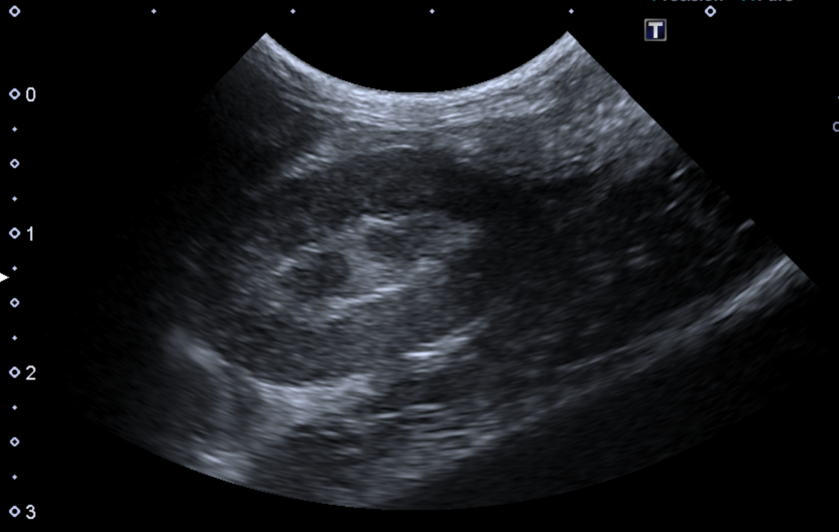

超音波検査

体の表面から超音波を当てて、内臓の状態をリアルタイムで観察する検査です。特に未避妊雌のウサギでは卵巣子宮疾患の評価で重要になり、子宮腺癌や子宮水腫、子宮蓄膿症を早期に発見する助けになります。他にも肝臓や腎臓、膀胱といった内部構造の評価ができます。結節や腫瘤の有無、組織の変性状態などを推測でき、これはⅩ線検査よりも超音波検査の方がわかりやすいです。膀胱は沈殿物や壁の厚み、感染や結石の判断材料になります。